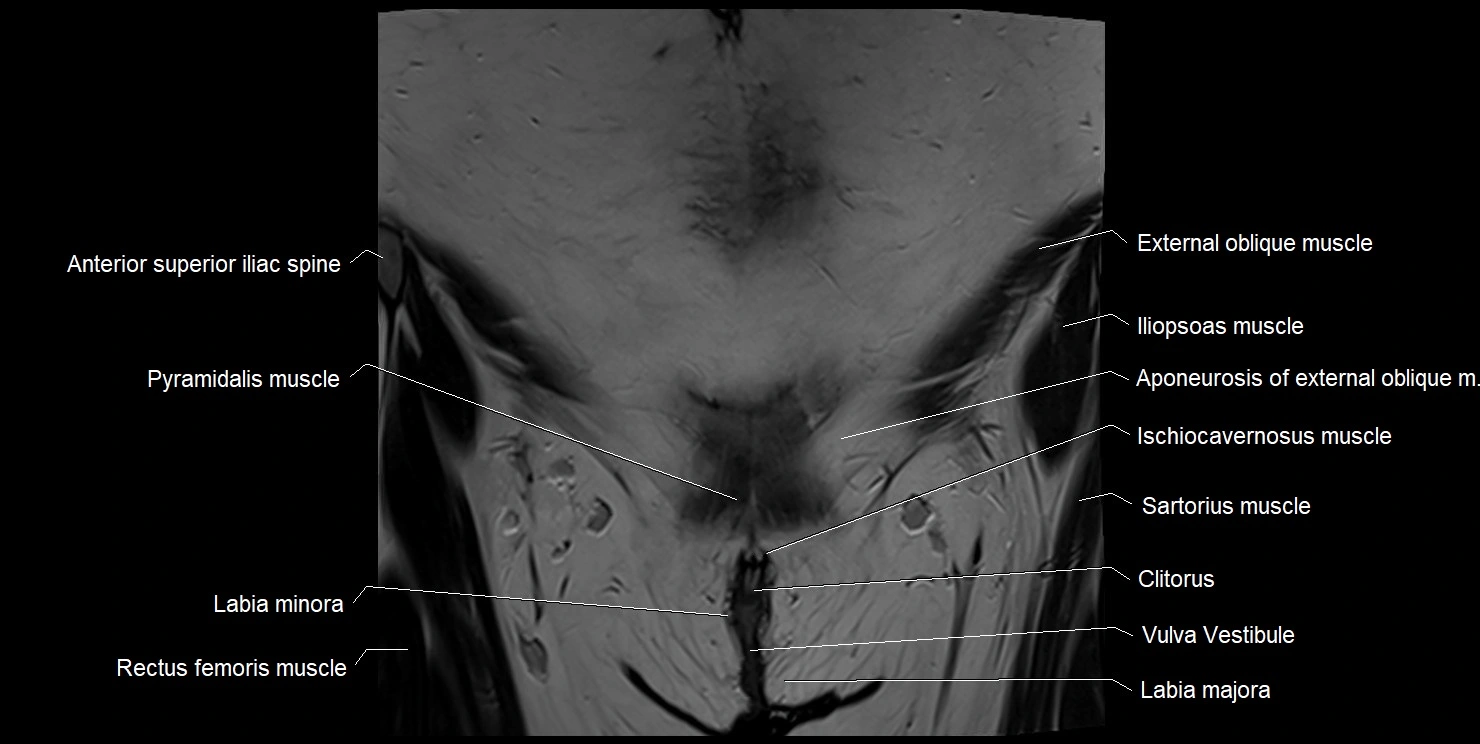

- Anterior superior iliac spine

- Clitoris

- Labia majora

- Labia minora

- Mons pubis

- Pyramidal muscle (pyramidalis muscle)

- Rectus femoris muscle

- Sartorius muscle